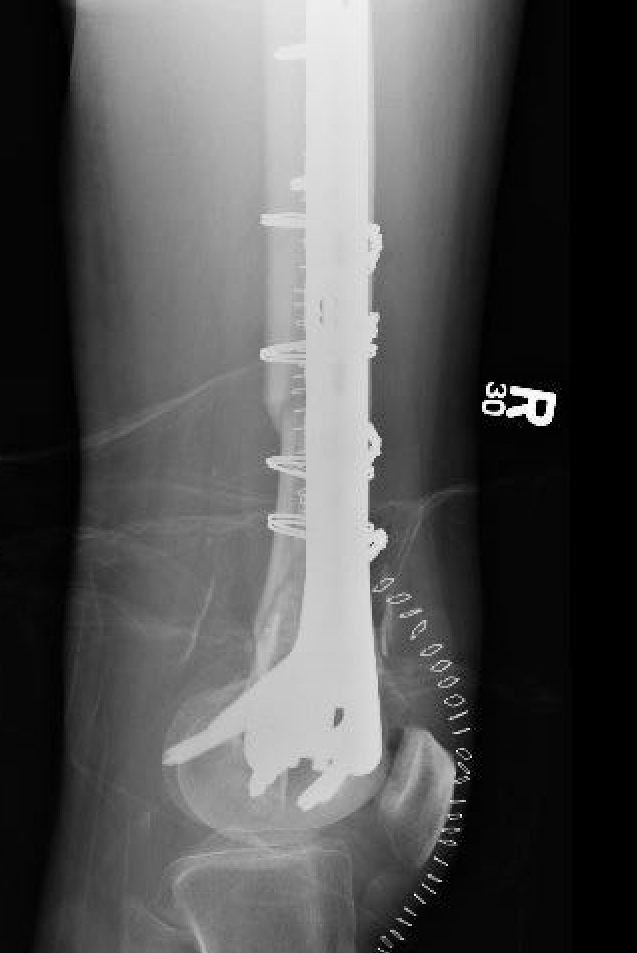

AO Type A: Supracondylar / Extra-condylar

Xray

Options

Lateral plate

Retrograde IM nail

Retrograde Nail

Surgical Technique